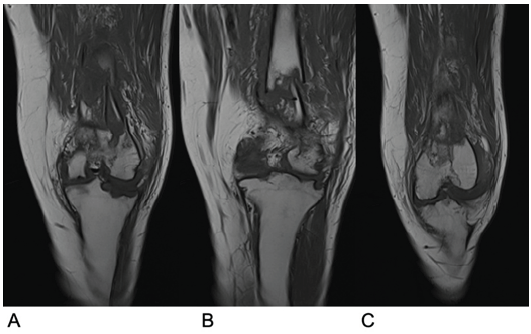

Figure 5: Magnetic resonance imaging scan of the left knee following repeat injury. (a) Coronal view of the anterior section of the joint. (b) Coronal view of the middle section of the joint. (c) Coronal view of the posterior section of the joint.

An MRI (Fig. 5) displayed normal marrow tissue and significant improvement in bony architecture compared to the initial MRI, with no suspicion of underlying lesions. A second open reduction and internal fixation was performed, with extensive samples taken for histological and microbiological analysis. Histological evaluations indicated acute inflammatory changes consistent with an acute fracture, and granulomas were absent. ZN staining and mycobacterial tissue culture were negative, confirming no recurrence of TB infection. The patient had a normal recovery following this surgical intervention, with tissue samples confirming successful treatment of TB. X-rays showed satisfactory alignment and implant placement (Fig. 6). The patient was pain-free while weight-bearing with one crutch at 12 weeks after the final surgery.